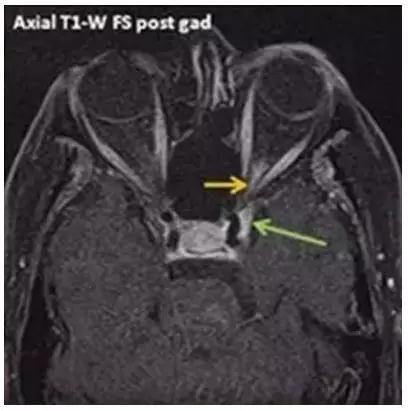

9點(diǎn)后,病房陸續(xù)迎來了4位新住院患者,其中一位是免疫性眼病患者,來自安徽,凌晨5點(diǎn)就從家出發(fā)來我們新院了,她頭痛劇烈,受累眼睛視力幾近失明,行走都需要她女兒攙扶,她是專門奔我們科而來,她的病名叫“Tolosa Hunt綜合征”,該病是罕見病中的罕見病,發(fā)病率只有1/100萬(wàn),該病診治困難,個(gè)體化治療非常重要。免疫性眼病是我們科的診療特色,診療經(jīng)驗(yàn)較為豐富,僅通過一天的治療,患者癥狀明顯改善。